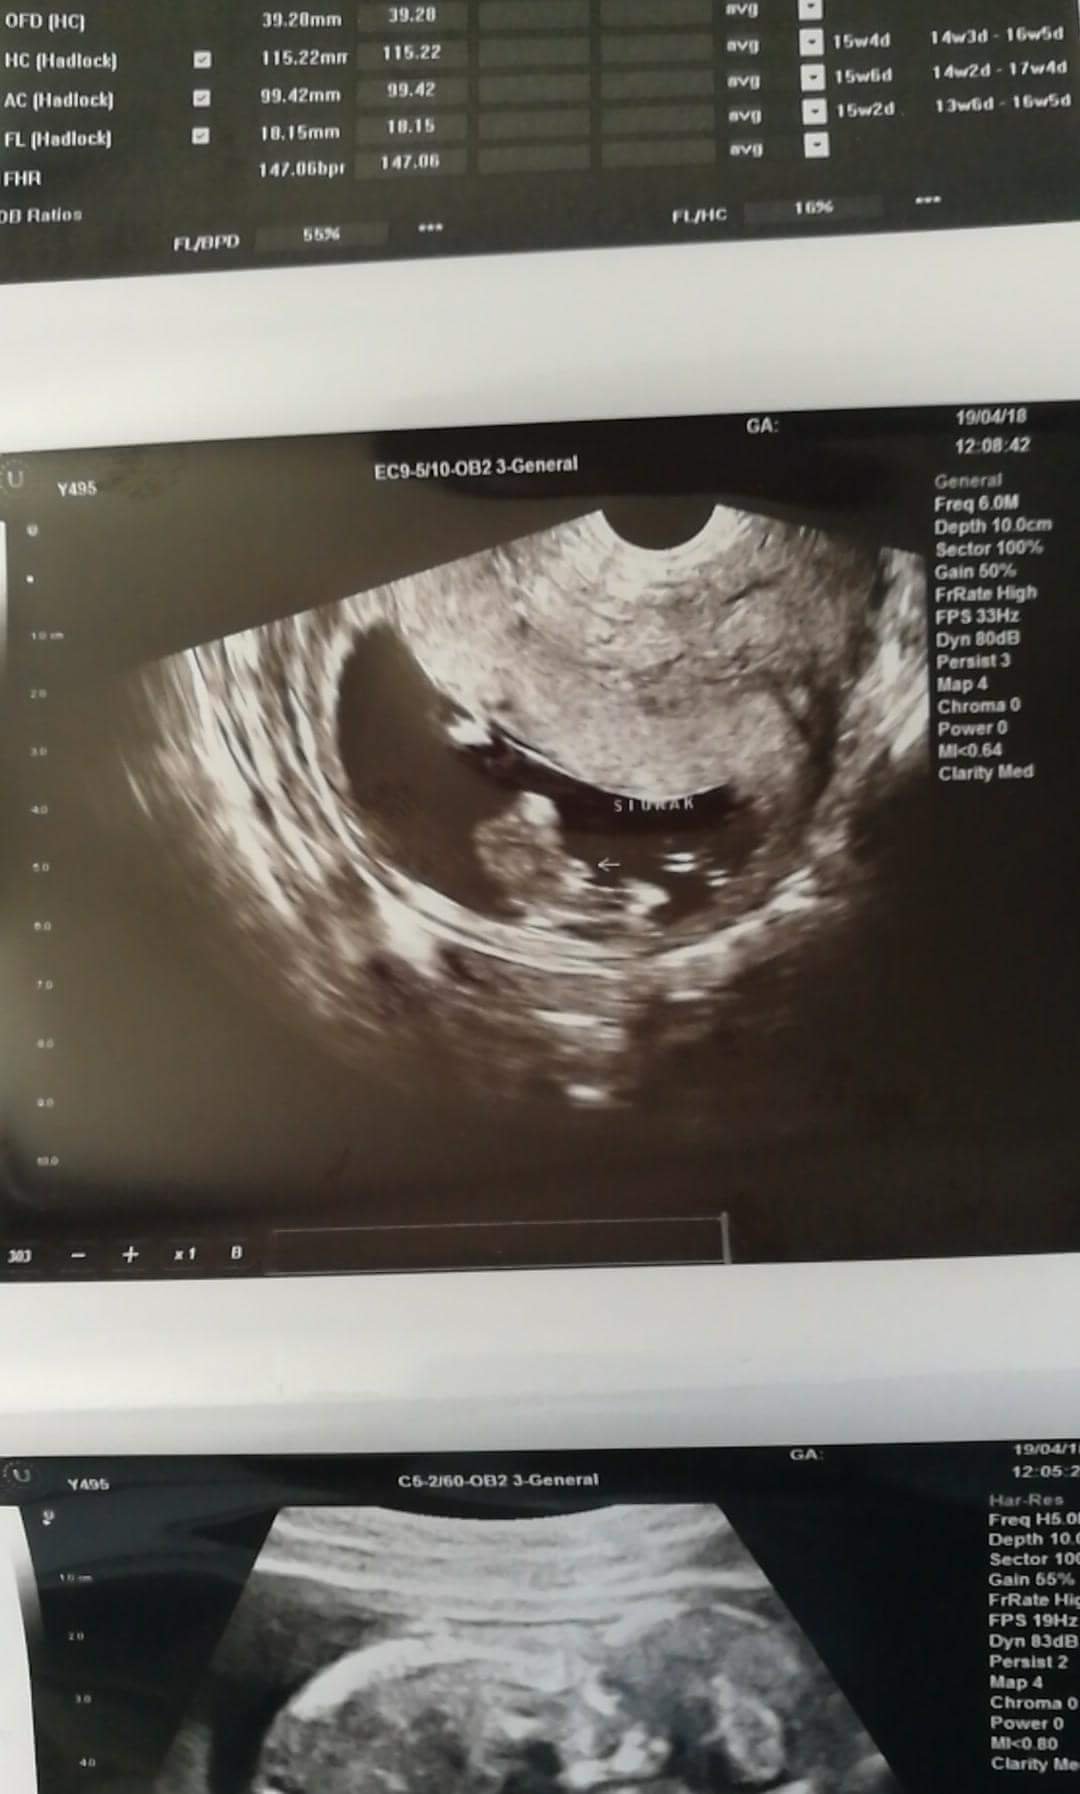

Dziś USG miałam takie normalne mniej widoczne niż prenatalne... A może sprzęt ma stary... Nie wiem . Tak czy siak niby z 12+6 widział chlopaka... Ale wolę nie nastawiać się i czekam do mają żeby to potwierdzić :eek: